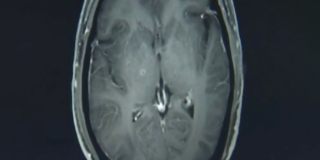

Man had hundreds of tapeworms in brain, chest after eating undercooked pork | Fox News

Jianrong said his patient is doing well after one week, but the long-term effects from the massive infestation are unclear.